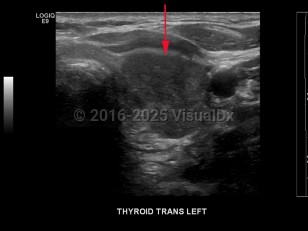

Signs and symptoms include a neck lump or swelling, neck pain, hoarseness, dysphagia, dyspnea, and/or persistent cough. Erythroderma may rarely be a cutaneous manifestation of malignancy.

Thyroid cancer is classified based on histologic features:

- Papillary thyroid cancer – The most common type of thyroid cancer (approximately 85% of cases), often with diagnosis at an early stage with good overall prognosis. Characteristic histologic findings include psammoma bodies, cleaved nuclei with an "Orphan Annie" appearance, and the formation of papillary structures. Of note, it is now suggested that the encapsulated follicular variant of papillary thyroid carcinoma, which has a very low risk of adverse outcome, be reclassified as noninvasive follicular thyroid neoplasm with papillary-like nuclear features.